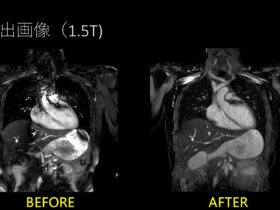

落ちムラ無し!!B-TFEでもSTIR!